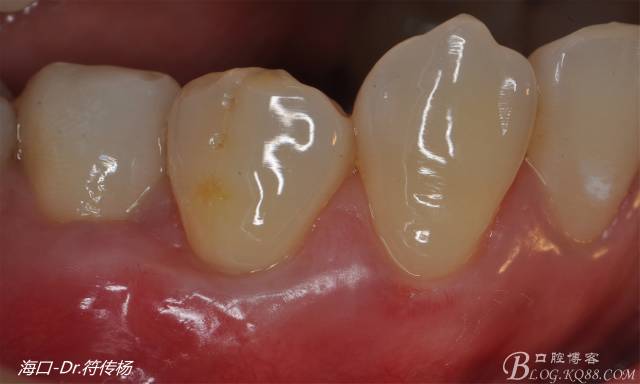

術(shù)后十天牙齦一期愈合

術(shù)后兩月